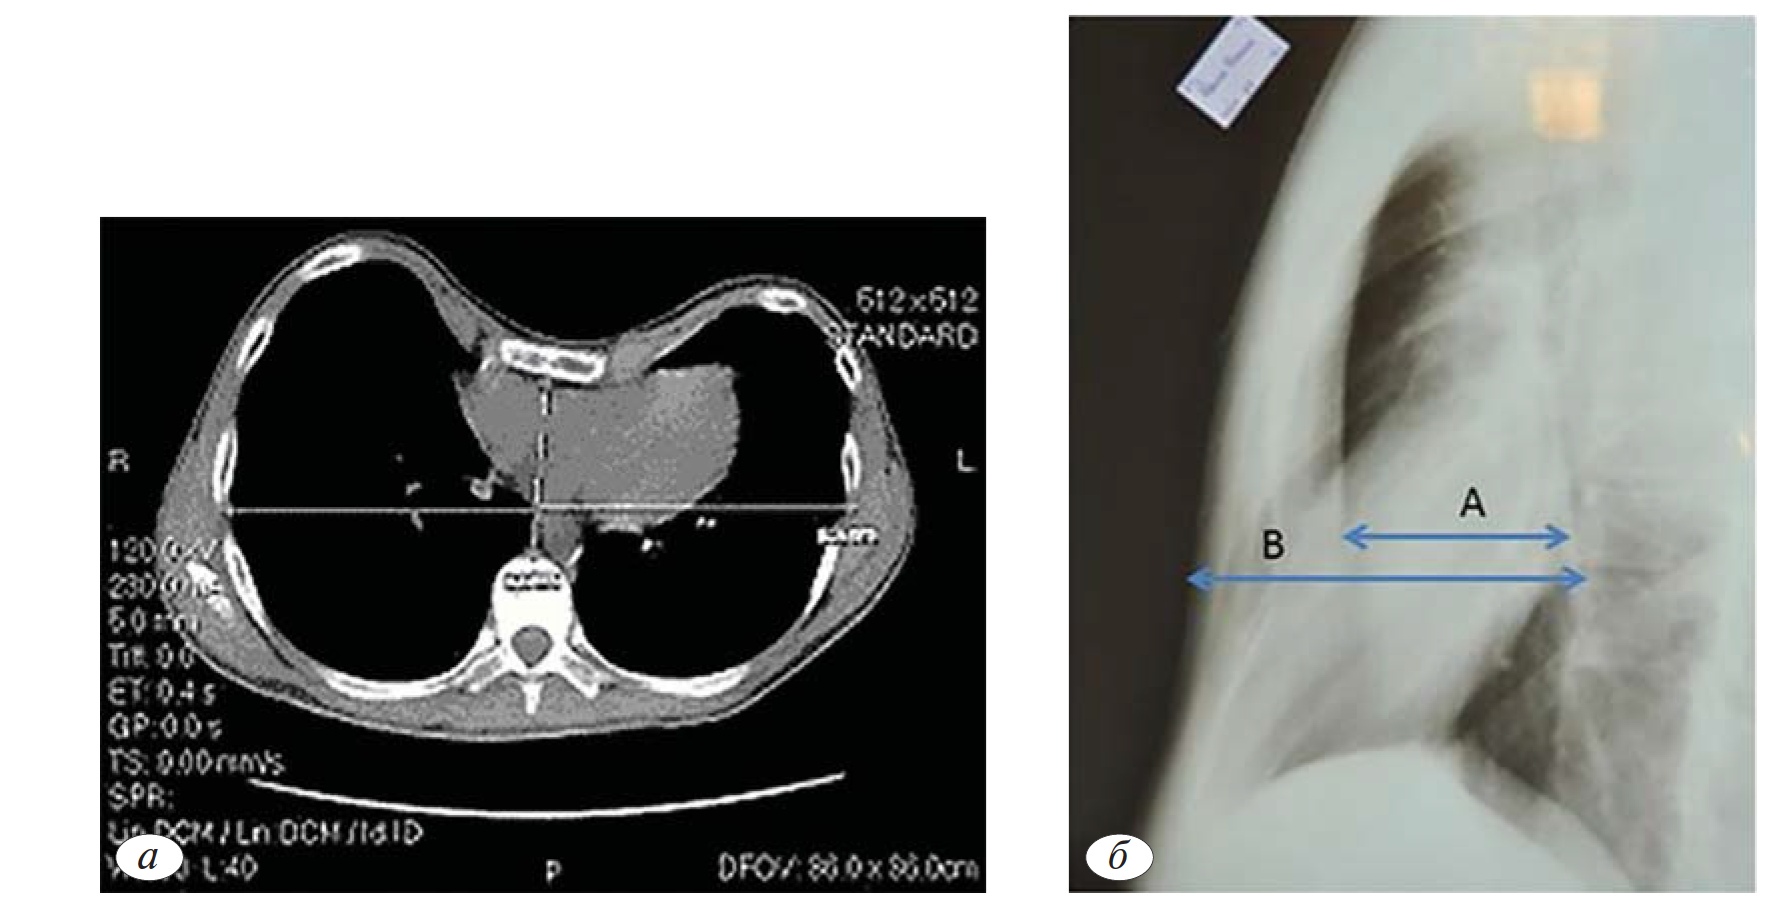

На спиральной компьютерной томографии определениндекс Haller (11) и характеристики по классификации Y. Park (10). На рентгенографии определен индекс Gizycka (9) (рис. 2).

Исходя из полученных данных, у женщины имел место рецидив Воронкообразной деформации грудной клетки до III степени по индексу Gizycka (0,45), индекс Haller (3,5), IIA1 тип — ассиметричный локальный тип по классификации Y. Park.

Рис. 2.а — КТ с определением индекса Haller и отношение по классификации Y. Park; б— определение индекса Gizycka.